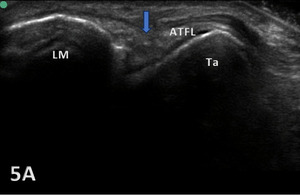

PARTIAL TEAR OF ATFL

Figure 5A: The ATFL exhibits heterogeneous hypoechogenicity with some calcifications. This finding reveals a chronic partial tear (blue arrow). ATFL, anterior talofibular ligament; LM, lateral malleolus; Ta, talus.